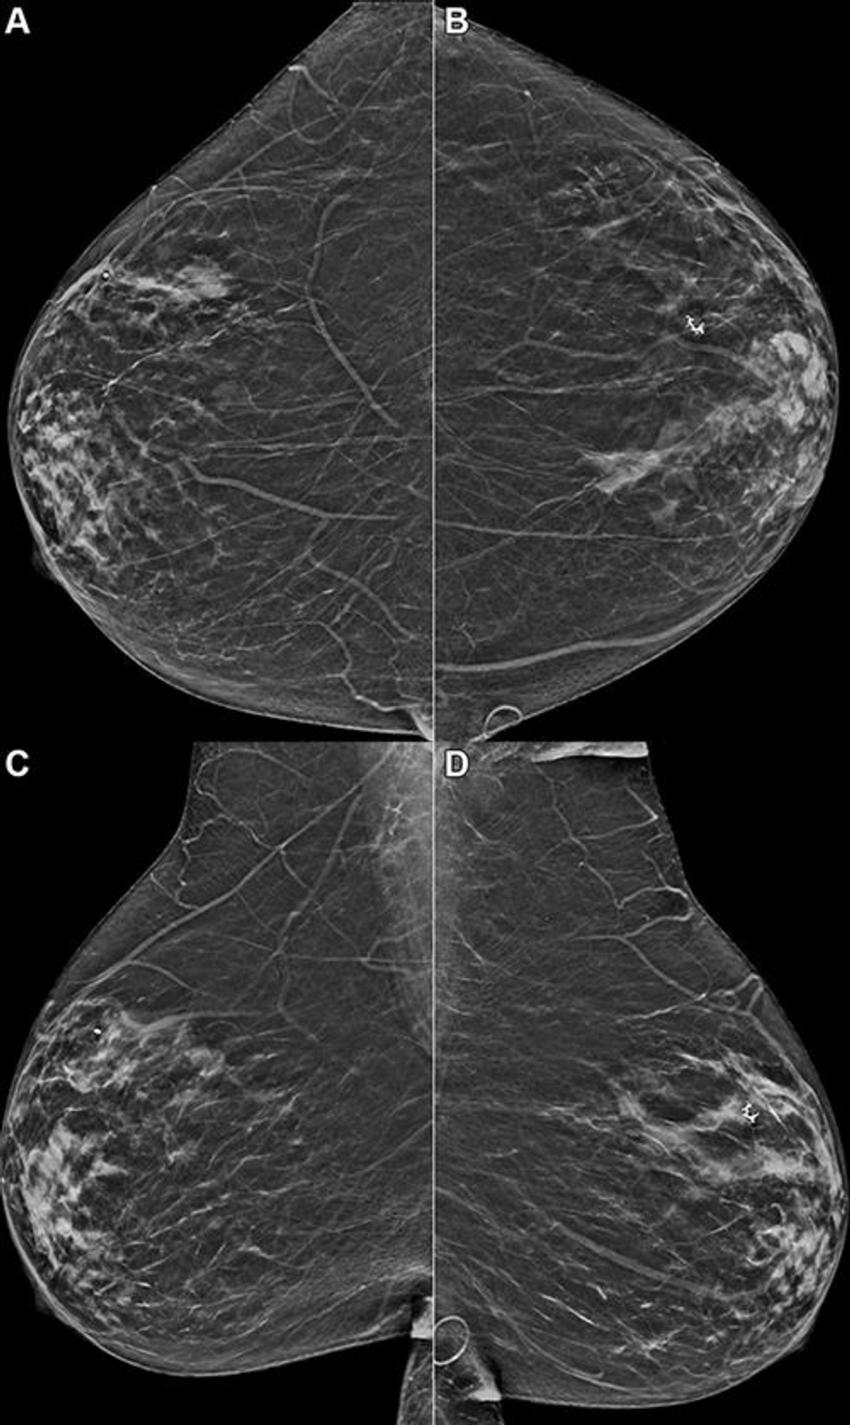

Figure 4. Example mammogram assigned a false-positive risk score of 1.0 in a 59-year-old Hispanic patient with heterogeneously dense breasts. Bilateral reconstructed two-dimensional (A, B) craniocaudal and (C, D) mediolateral oblique views are shown. The algorithm predicted cancer within 1 year, but this individual did not develop cancer or atypia within 2 years of the mammogram.